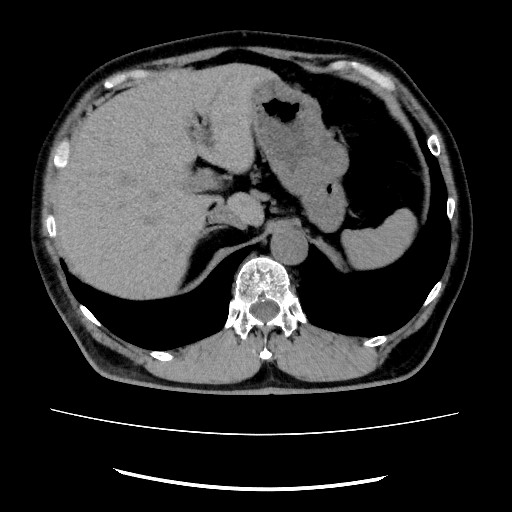

CT検査

マルチスライスC T 低線量による最適な撮影が可能 3D画像にも対応

肛門周辺の病変を詳しく調べることができます。肛門周囲膿瘍の広がりや痔瘻の走行、直腸癌や進行大腸癌、前立腺や子宮.卵巣の病気なども検出可能です。

この撮影法は、従来の腹部CTとは異なり、うつぶせの状態で撮影を行います。また、CTのスライス(断面)角度を直腸の走行に合わせて調整することで、肛門周辺の病変をより詳しく観察できるようになります。